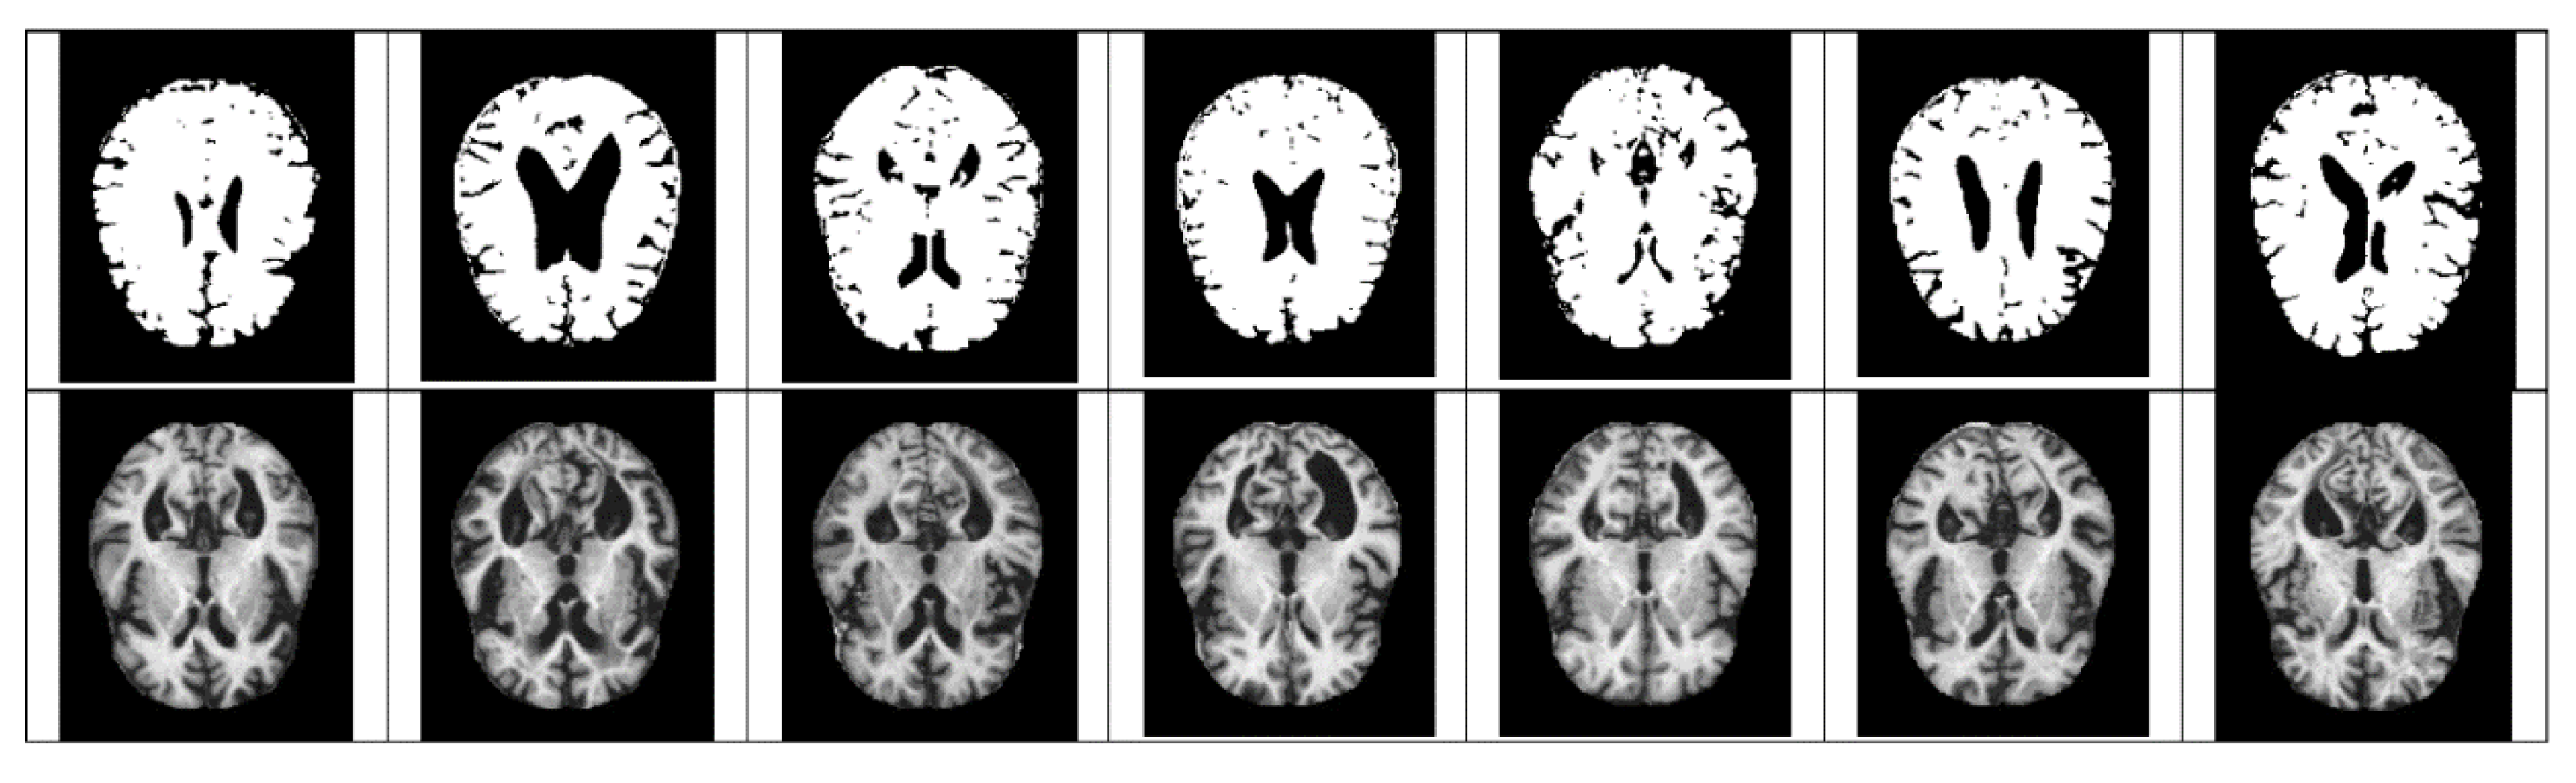

- The size space of pixels constituting the Alzheimer’s MRI data set is [0, 255]. Among them, patients with AD with reduced hippocampus will have more pixels close to zero than normal people. On the premise of this, the average value of pixel intensities in each MRI image is set as a threshold value. Alzheimer’s should recognize changes in size contraction rather than changes in brain function. Based on this information, it is necessary to set the space as an important feature for the color information of MRI rather than a feature representing the shape of the brain.